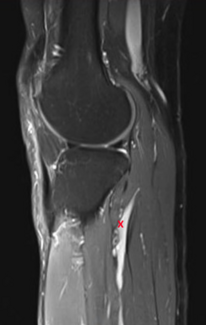

This article presents a case series and systematic review on the clinical outcomes following surgical excision of common peroneal nerve intraneural ganglia.